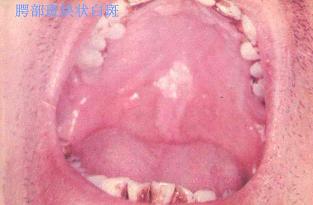

口腔粘膜病组图